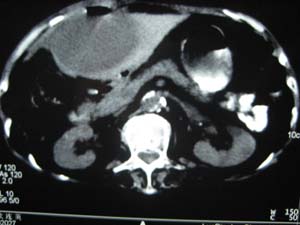

标题: CT15625:女性78Y,十天前胃镜示胃穿孔,现低热 [打印本页]

标题: CT15625:女性78Y,十天前胃镜示胃穿孔,现低热

肝脓肿/膈下脓肿?

膈下脓肿

隔下肿脓.

支持--膈下脓肿

膈下及肝脓肿。

考虑多发性肝脓肿。